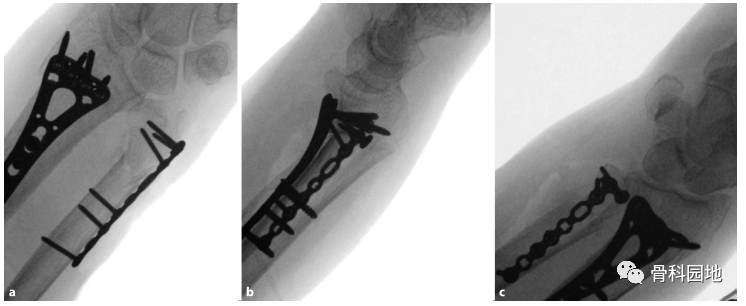

骨折可使用复位钳复位。根据骨折类型,可以用克氏针将远端碎片暂时固定在桡骨远端。b为确保解剖复位,进行透视检查。c评估远端尺桡关节。

a透视确认后,将钢板完全固定。元旦螺钉不要突出到远端尺桡关节。b进行透视成像以评估完全固定钢板的位置。